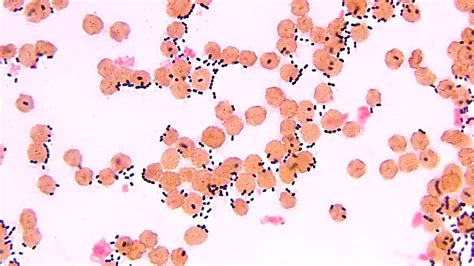

Lo Streptococcus pneumoniae è un batterio Gram-positivo, alfa-emolitico, capsulato e aerobio facoltativo. La sua presenza è ubiquitaria, colonizzando normalmente le vie respiratorie superiori di oltre il 30% dei soggetti sani. Tuttavia, in presenza di concause predisponenti, come infezioni virali, traumi toracici o altre malattie, questo batterio può raggiungere le vie respiratorie profonde e scatenare un'infezione severa.

La diagnosi di infezione da pneumococco si basa su una combinazione di sospetto clinico e accertamenti microbiologici. In un paziente sintomatico, la presenza di diplococchi lanceolati Gram-positivi e dotati di capsula in campioni biologici è suggestiva di infezione pneumococcica.

Per ottenere una conferma diagnostica, è fondamentale l'esecuzione di una coltura batterica, in quanto alcuni streptococchi possono presentare una morfologia simile allo pneumococco. In presenza di campioni naturalmente contaminati, come l'espettorato, l'utilizzo di terreni selettivi contenenti farmaci a cui lo pneumococco è insensibile, come l'acido nalidixico, può essere utile.

Lo pneumococco viene distinto da altre colonie di streptococchi viridanti attraverso il test di sensibilità all'optochina, risultando positivo. La capsula, elemento chiave per l'identificazione sierotipica, può essere meglio evidenziata tramite la reazione di Neufeldt, che sfrutta l'applicazione di un antisiero anti-pneumococcico polivalente e blu di metilene. In seguito a questa reazione, la capsula appare notevolmente ingrossata per la precipitazione del materiale polisaccaridico capsulare.